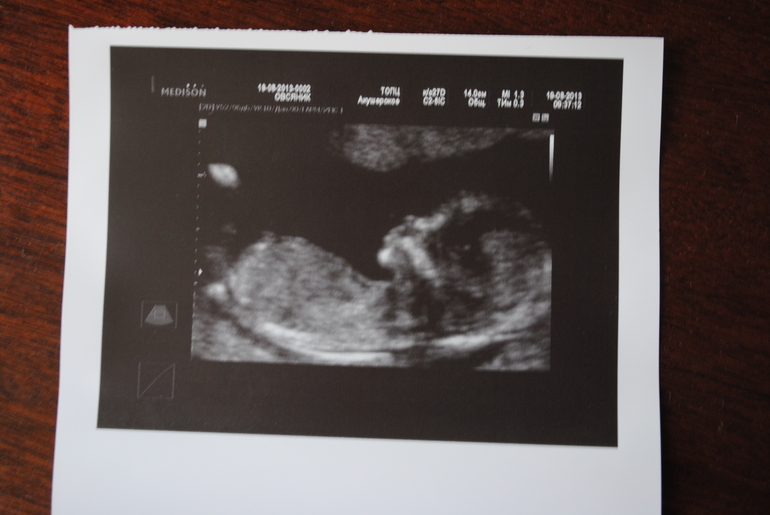

Ольга 12 лет Первое фото малыша Посмотрите еще 20 записей на эту тему Отменить Ответить Рита у вас такой профиль отчетливый уже))) 03.09.2013 Ответить Катя Лапочка маленький (или маленькая))) А нам на скриннинге не дали фотку(( хочу теперь сама записаться на внеплановое узи 30.08.2013 Ответить Аринка Такой лапочка!!!!!!! Губки трубочкой и нос - курносик! Не сказали пол????? 30.08.2013 Ответить Пнул. 13-14 недель. Вес мой. Чаты Беременных Выберите чат: Январята-2026 Февралята-2026 Мартята-2026 Апрелята-2026 Майчата-2026 Июнята-2026 Июлята-2026 Августята-2026